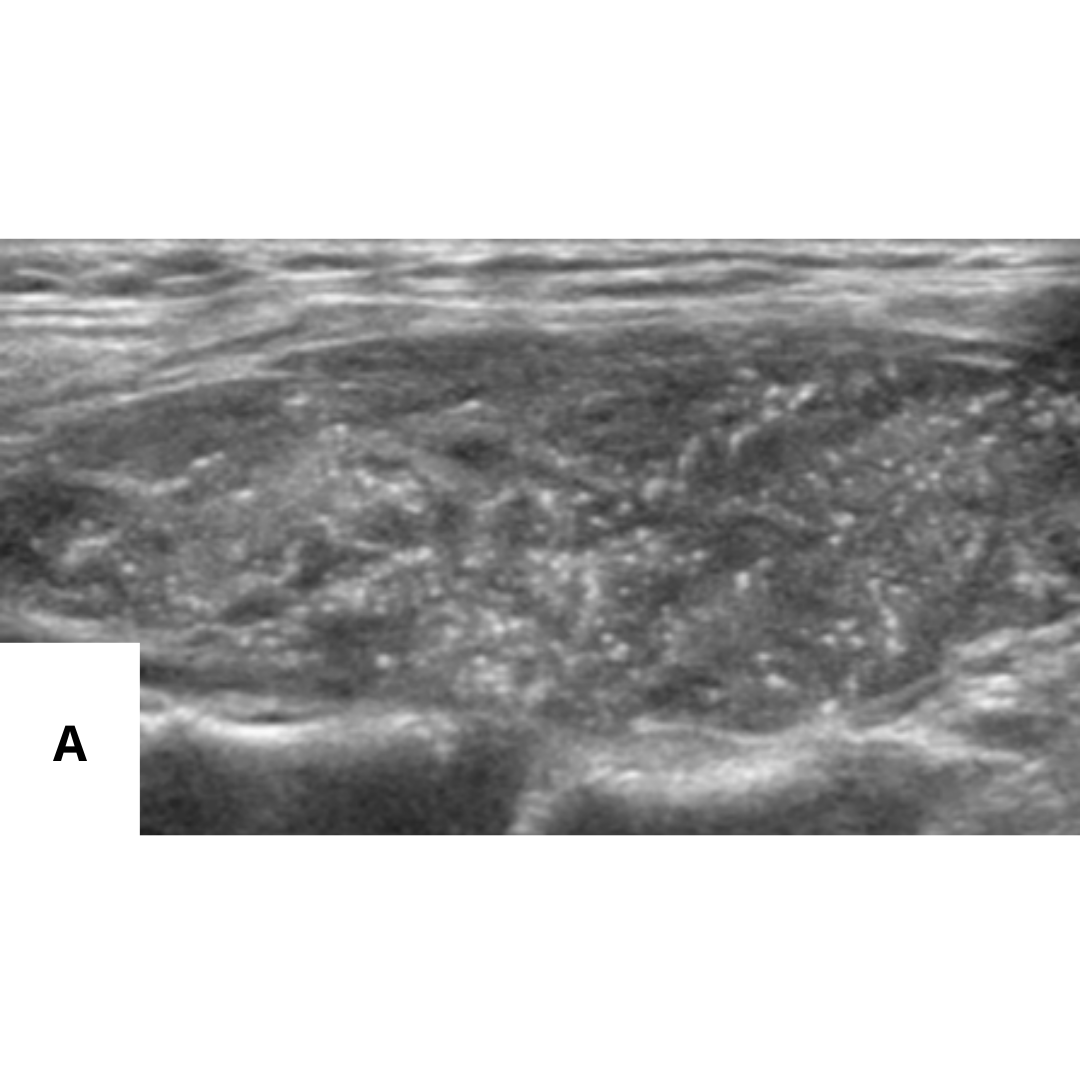

En ambas presentaciones existirá un alto porcentaje de visualización de ganglios cervicales aumentados de tamaño, con MCC difusas, similares a las que se presentan en el parénquima tiroideo.

Fig4. (A) En lóbulo tiroideo derecho, 1/3 medio, se visualiza nódulo sólido, hipoecogénico, mal delimitado con múltiples calcificaciones puntiformes en su interior (cuerpos de Psamoma). (B) Estas también se presentan de manera difusa periféricas al nódulo. (C) En Región cervical derecha, GIV, se visualiza ganglio cervical aumentado de tamaño, con múltiples imágenes puntiformes hiperecogénicos en su periferia e interior sugerente de microcalcifcaciones.